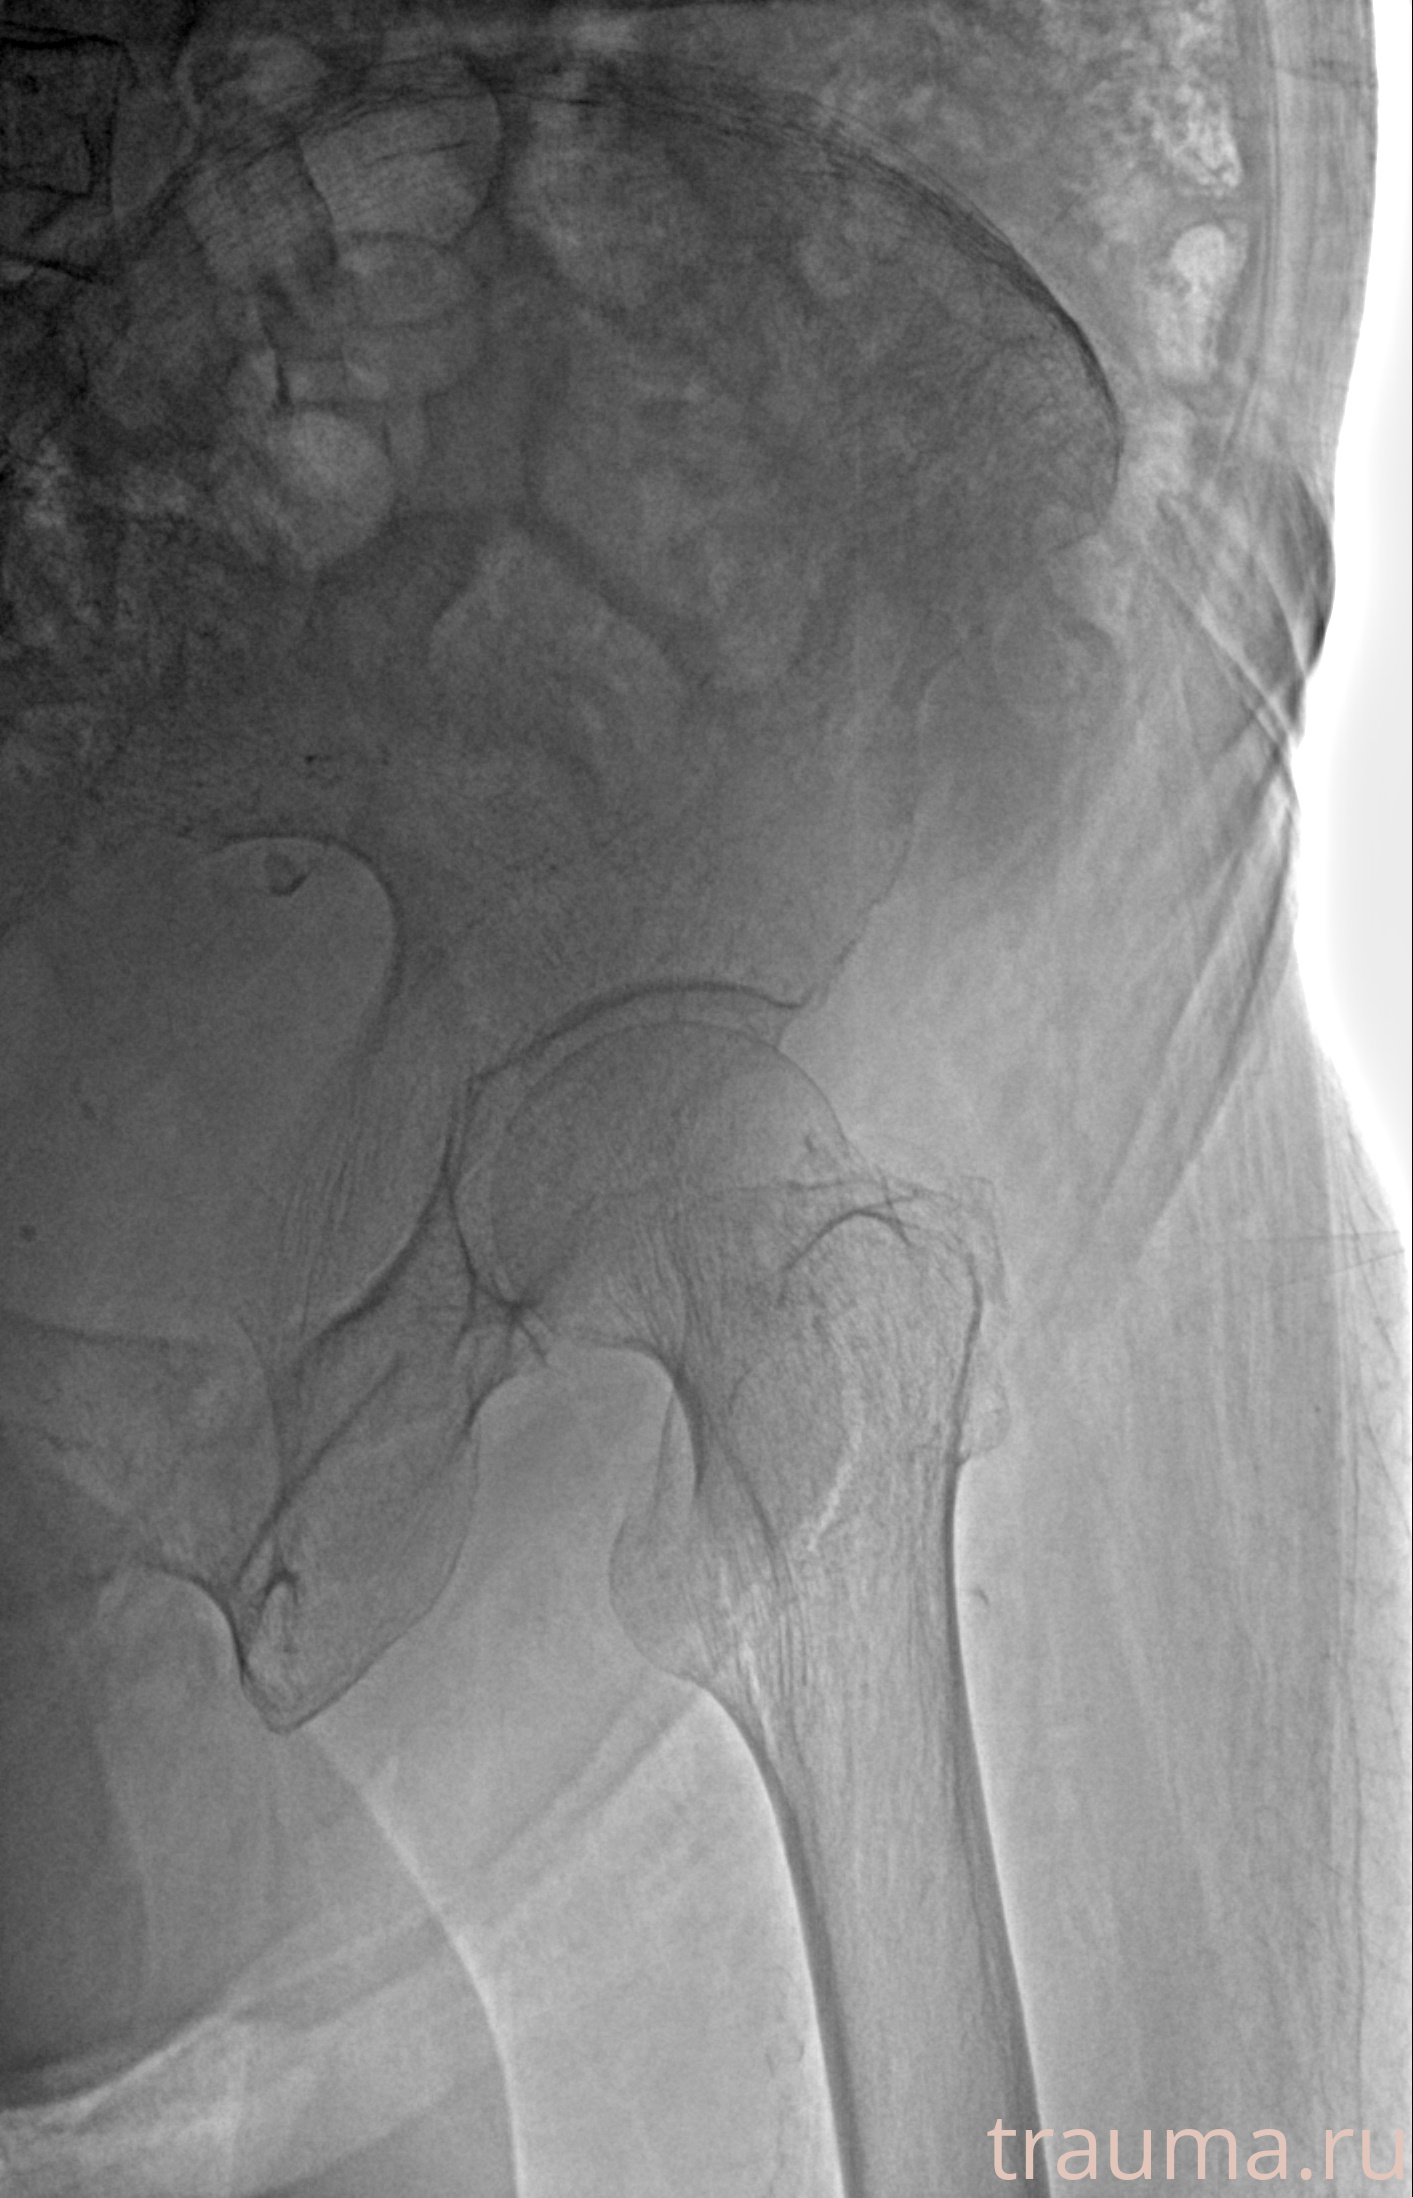

Рентгенограммы

Рентген на дому: по вашему адресу приезжает врач-рентгенолог, травматолог-ортопед с мобильным рентгеновским аппаратом, проводит диагностику травмы или заболевания, делает необходимые рентгенограммы, дает рекомендации по дальнейшему лечению. Получить качественные снимки в домашних условиях возможно благодаря уникальной методике, разработанной МосРентген Центром для института  Склифосовского

при переломе шейки бедра и пневмонии от компании МосРентген Центр - партнера Института имени Склифосовского